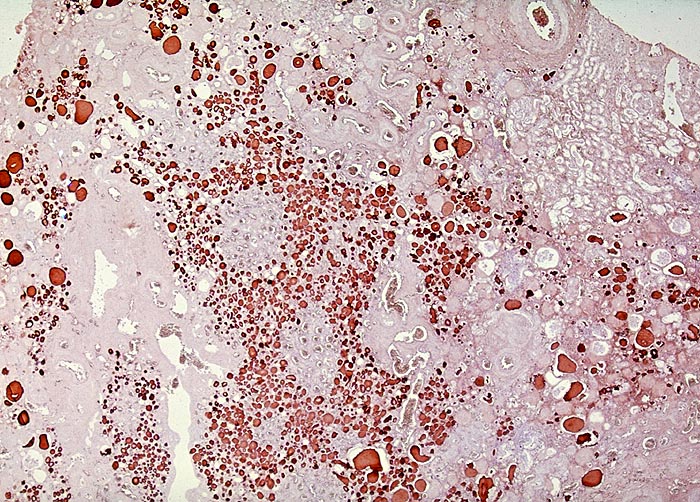

Chronische Pyelonephritis: neben unverändertem Parenchym herdförmige lymphoplasmohistiozytäre Infiltrate (bei akutem Schub zusäztlich neutrophile Granulozyten). Granulationsgewebe im Interstitium führt schliesslich zur Narbenbildung und Nierenschrumpfung.

Pseudostrumabild: Gruppen erhaltener dilatierter Tubuli mit abgeflachtem Epithel enthalten sogenanntes Harnmukoid (Tamm-Horsfall Protein und/oder IgA). Bei kindlicher Pyelonephritis häufig auch Lymphfollikel. Pseudostrumaherde sind ein wichtiger Hinweis, aber kein Beweis für chronische Pyelonephritis.